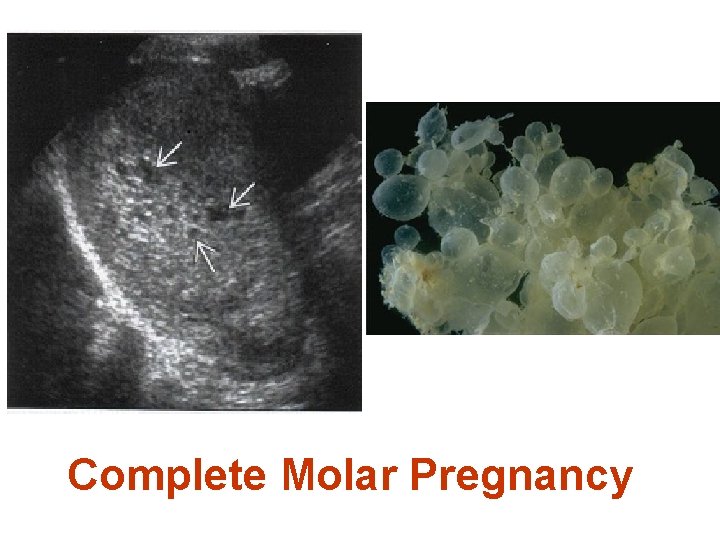

Complete H. Mole Microscopically Enlarged, edematous villi and abnormal trophoblastic proliferation that diffusely involve the entire villi No fetal tissue, RBCs or amnion are produced Macroscopically, these microscopic changes transform the chorionic villi into clusters of vesicles with variable dimensions “ like bunch of grapes" No fetal or embryonic tissue are produced Uterine enlargement in excess of gestational age. Theca-lutein cyst associated in 30%

1 -Trophoblastic proliferation 2 -Hydropic Degeneration Complete hydatidiform mole: Microscopically Enlarged, edematous villi and abnormal trophoblastic proliferation that diffusely involve the entire placenta

Complete hydatidiform mole: Macroscopically, these microscopic changes transform the chorionic villi into clusters of vesicles with variable dimensions the name hydatidiform mole stems from this "bunch of grapes"

Complete Molar Pregnancy

Complete hydatidiform mole. The classic "snowstorm" appearance is created by the multiple placental vesicles.

Complex intrauterine mass containing many small cysts (Snowstorm appearance) What is the most likely diagnosis? Hydatidiform (Vesicular) mole

1 -What Is The Most Likely Diagnosis? The snowstorm pattern on U/S& The abnormally high h. CG level are diagnostic of Vesicular Mole Probably complete V. mole

Why It Is Probably Complete V. Mole? It demonstrates the typical U/S appearance of complete V. mole : a complex, echogenic intrauterine mass containing many small cystic spaces. Fetal tissues and amnionic sac are absent However the final differentiation is after histopathology.

Meticulous histopathological examination revealed: ØVilli have extensive stromal edema ØAbnormal trophoblastic proliferation ØNo embryonic or fetal tissue or RBCs These findings are diagnostic of: Complete Hydatidiform Mole